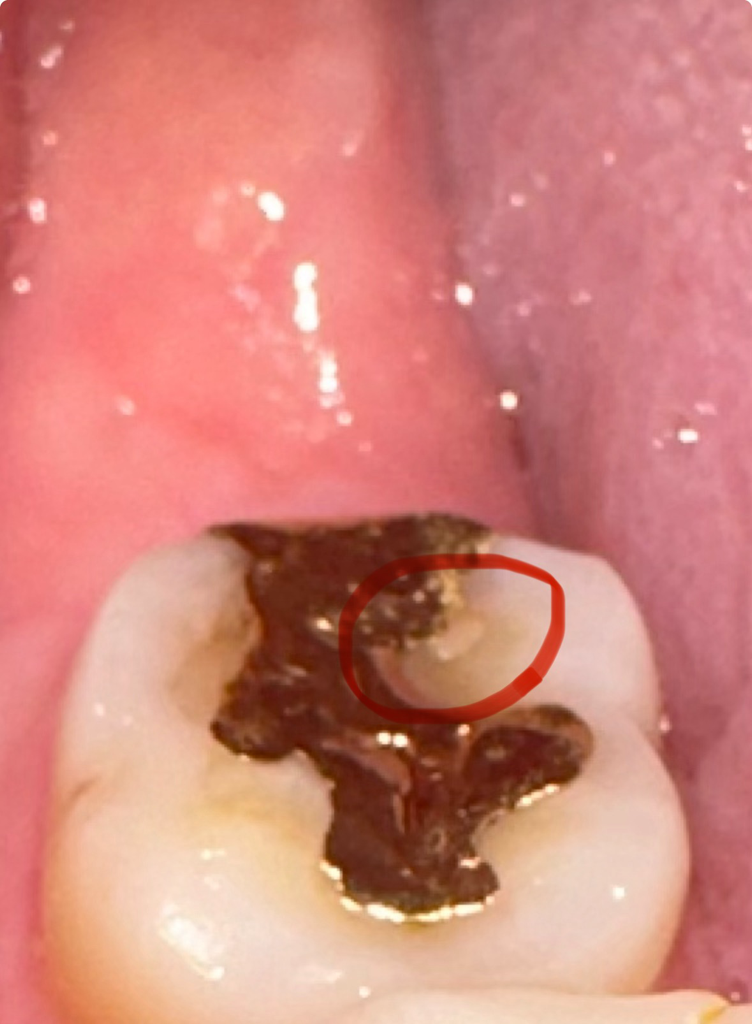

골드 인레이 주변으로 치아들이 많이 떨어져 나간거 같은데 이물질이 껴서 그럴수도 잇으니 치과에 가셔서 검진을 한번 받아보세요.

현재 금 인레이틈으로 충치가 발생하였을 가능성이 있어보입니다. 따라서 가능한 빠른시일내에 정확한 상태 확인후 치료를 위해 치과 진료를 받길 권합니다.

금인레이 보철물이 일부 탈락하고 하방 접착제가 남아있는것이 아닌가 예상됩니다 치과에서 보다 정확한 검사를 받아보시기바랍니다